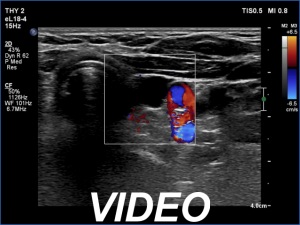

Second examination two years later (third row of images)

Clinical data: The patient had no complaints, she was on the 7th gestational week and came to follow-up.

Ultrasonography was unchanged. Connective tissue was found in the upper part of the left thyroid bed while there was a cystic lesion in the lower half. On the location, the lesion corresponded to a parathyroid cyst. The dimensions of the cyst were 8x6x13 mm, width, depth and length, respectively.Suggestion: to increase the dose of the levothyroxine to daily 150 micrograms. TSH in 6 weeks.

Comment. On the location of the cystic lesion, this is probably of parathroid origin. Based on the stably undetectable thyroglobulin level, we have no reason to suggest that this would have oncological importance.